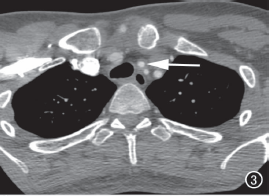

图3 头臂动脉管壁增厚,以左颈总动脉为著(箭)。